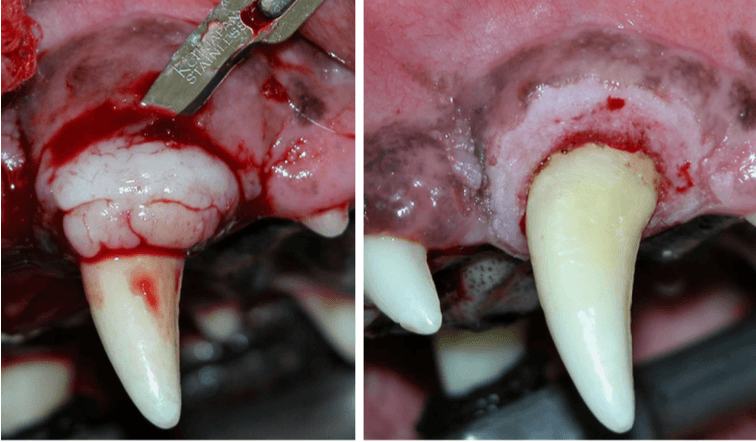

The procedure pictured here is used when the part of the gum being resected is hyperplastic.

What is a gingivectomy?